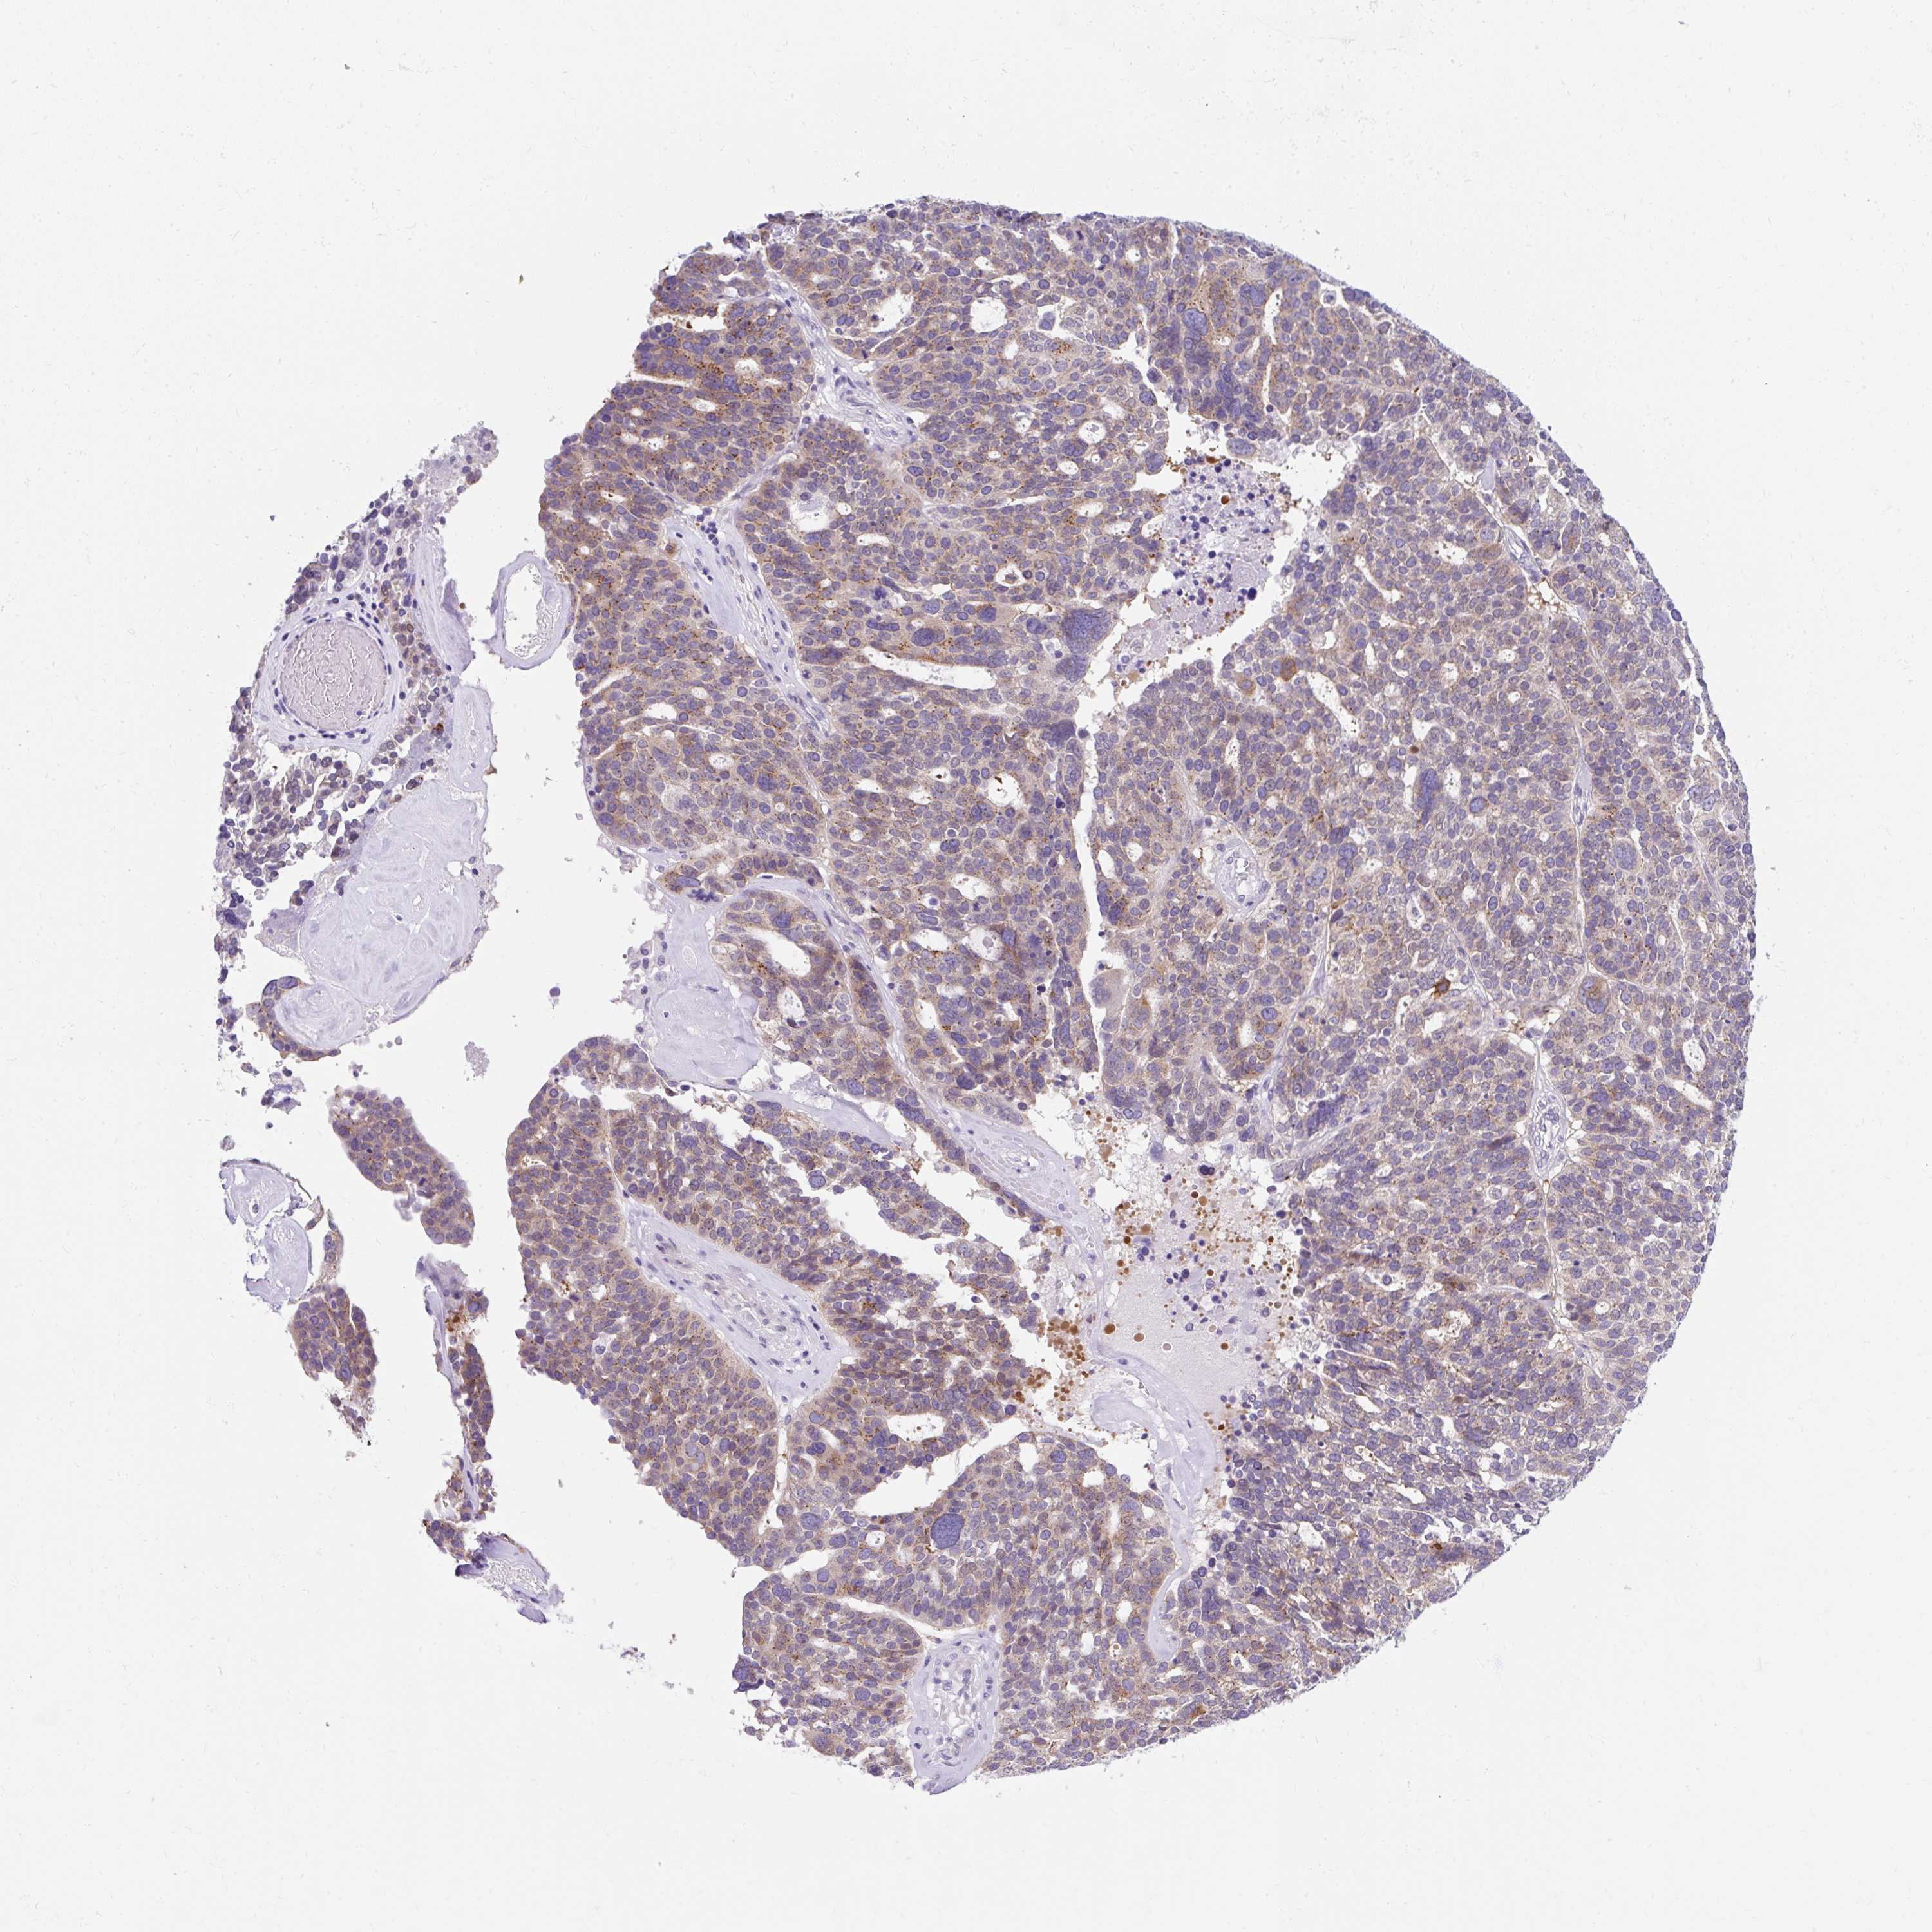

OVARIAN CANCER - Protein expressioni

A mouse-over function shows sample information and annotation data. Click on an image to view it in a full screen mode. Samples can be filtered based on level of antibody staining by selecting one or several of the following categories: high, medium, low and not detected. The assay and annotation is described here.

Note that samples used for immunohistochemistry by the Human Protein Atlas do not correspond to samples in the TCGA dataset.

Antibody stainingi

Antibody staining in the annotated cell types in the current human tissue is reported as not detected, low, medium, or high, based on conventional immunohistochemistry profiling in selected tissues. This score is based on the combination of the staining intensity and fraction of stained cells.

Each image is clickable and will lead to virtual microscopy that enables deeper exploration of all samples and also displays staining intensity scores, fraction scores and subcellular localization as well as patient and tissue information for each sample.

Antibody HPA051808

Staining

High

Medium

Low

Not detected

Intensity

Strong

Moderate

Weak

Negative

Quantity

>75%

75%-25%

<25%

None

Location

Nuclear

Cytoplasmic/membranous

Cytoplasmic/membranous,nuclear

Cystadenocarcinoma, serous, NOS

Carcinoma, NOS

Cystadenocarcinoma, mucinous, NOS

Carcinoma, endometroid